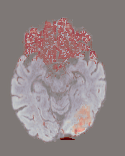

While ACAT revolves around generating counterfactuals, its primary strength lies in accurately identifying pathological regions, which are subsequently employed in a classification pipeline. On the other hand, it falls short in producing credible counterfactual examples, an issue we aim to address in this study. An illustration of this phenomenon is depicted in Figure 2, where we can observe how ACAT is able to generate a saliency map that approximately identifies the pathological region (e, bottom row). However, in the counterfactual example, the lesion remains visible (e, top row). In contrast, our approach not only refines the saliency map but also generates a counterfactual image where the pathology is completely eliminated (f).

In our work, we aim to tackle this challenge by proposing a two-step approach. First, we employ ACAT to obtain initial saliency maps, which provide a rough identification of the regions requiring modification. Then, we introduce a novel sampling technique from diffusion models that enables targeted modifications to these regions while preserving the remainder of the image unchanged. By fusing both components at each timestep, we achieve a seamless transition between the edited and unedited parts, resulting in a realistic output. By considering the difference between the counterfactual example and the original image, we can also obtain the final anomaly map.

We observe that our sampling approach not only generates highly realistic counterfactuals but also enhances the initial saliency maps obtained in the first step using ACAT. This is possible because the selected regions may not undergo complete modification by the diffusion model, allowing for the preservation of healthy anatomical features identified in the initial attribution maps. A visual representation of our approach is presented in Figure 1.

When computing with Eq. (9), the sum of the two components may not produce a perfectly coherent result. However, the incoherence is resolved by the next diffusion step, which fuses the two components better. This would not be the case if we simply computed with DDPM and then applied the mask only at the end of the sampling process. An illustration of this effect is presented in Figure 3, where we can observe how the normal image, generated by applying the mask solely at the conclusion of the sampling process (b), exhibits some artifacts and lacks a seamless transition between the edited and unedited regions.

In Figures 2 and 4 we display examples of healthy images and anomaly maps obtained with the different approaches. We can observe that f-Ano GAN is not able to generate credible counterfactuals and generally produces images of poor quality and unrealistic appearance. On the other hand, the approaches based on diffusion models are able to create more high-quality results. However, the ones obtained with CG and CFG seem to present some artifacts, which may not only impact the realism of the counterfactual examples but also the precision of the anomaly maps obtained from them. In order to better quantify the capability of these methods to accurately segment pathological areas, we compute the Dice scores of the anomaly maps they generate.